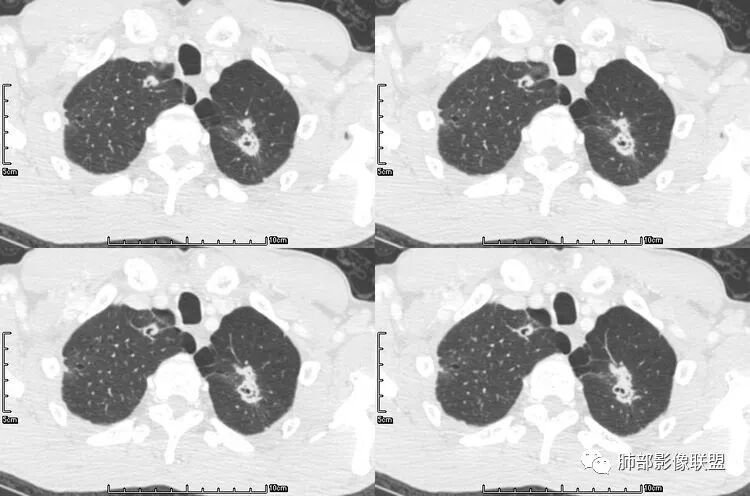

老年男性,咳嗽,咳痰带血2月,左下肺可见一团块影,深分叶,胸膜牵拉,可见坏死,坏死边界清,考虑恶性,双肺多发散在结节影,可见分叶,空洞,胸膜牵拉,考虑转移瘤;

双肺多发随机分布的结节伴空洞,部分囊内见空洞,分隔,壁结节呈假大空样改变,考虑肺腺癌伴转移或者全部为转移瘤。鉴别曲霉及血管炎,需要继续询问病史,有无免疫缺陷及鼻窦炎和肾功能的检查。

一开始看到多发空洞还有气囊,以为是金葡,但是病史不符合,部分空洞内有条索,左肺下叶病灶没有坏死,腺癌并肺内转移吧,鉴别曲霉,GPA;

张延军:双肺多发结节,空洞影,后者洞壁厚薄不均匀,部分腔内丝丝落落,呈分叶征,边缘见毛刺影,病灶大部分位于胸膜下,与血管相连,右肺下叶前基底段结节近段支气管截断,远端见空腔。左肺下叶病灶密度不均,背段支气管壁增厚,管腔狭窄。考虑1.双肺下叶占位性病变伴肺内空洞性转移 2.多原发的占位 3.肉芽肿性血管炎代排。

背景是慢阻肺背景。病灶是多发结节伴空洞,内部见结节影,即空洞内结节,符合得有:GPA,癌,结核,真菌(隐球菌,曲霉)

肺是发生转移瘤最多的脏器,几乎所有恶性肿瘤都可转移到肺,血行转移是最重要的转移途径。典型的肺转移瘤表现为多发圆形、大小不一的实性结节,边缘一般光整,多位于肺周边,多能明确诊断。空洞型肺转移瘤相对少见,约占肺转移瘤4%,其中70%为鳞癌转移;常见的空洞型肺转移瘤的原发恶性肿瘤多见于头颈部的鳞状上皮癌、胃肠道的腺癌和女性的生殖系统肿瘤以及其他部位的肉瘤等,组织学以鳞癌和腺癌最多见。

空洞型肺转移瘤成因尚不完全明确, 可能与鳞癌中心角化物排空 、腺癌黏液样退变后黏液排空 、肿瘤血供不足引起坏死 、肿瘤继发脓肿 、化疗等机制有关,其中部分薄壁囊腔样结可能是肿瘤细胞沿着原有的肺大泡或其它囊性结构生长或者肿瘤向小支气管侵犯引起活瓣性阻塞而形成 ,但无一种机制能解释全部现象。空洞或囊腔大小并不反映病情变化, 其临床意义不大, 而瘤灶的数目及大小, 特别是瘤灶实性成分的多少才可能更准确反映病情变化。肺癌形成空洞与其肿瘤本身性质有明显联系,肿瘤分化程度差,倍增时间越短,恶性程度越高,组织液化坏死形成空洞倾向越明显;鳞癌空洞偏大,内缘不规则,常易形成X线平片中癌梁样改变与CT中壁结节样改变;而腺癌空洞大小不定,洞内分隔明显,内缘不规则,且较难于形成壁结节等改变;合伴空洞的肿瘤边缘情况也对判断肿瘤性质有帮助。

国内文献将空洞的形态、壁的厚度及内壁情况将转移性空洞大致分为4大类:

(1)囊样空洞, 呈圆形或类圆形, 直径>15 mm,壁薄 (1 ~ 2 mm)而均匀 ,内壁欠光整 ;

(2)小环形空洞 ,呈圆形 ,壁薄 (2 ~ 4 mm)而均匀 ,直径≤15 mm, 内壁光整;

(3)泡样空洞, 呈圆形或类圆形 ,壁厚 ( >4 mm),内壁光整;

(4)不规则空洞, 洞腔形态不规则, 壁厚 ( >4 mm)且不均匀, 内壁不光整;

其中囊样空洞和小环形空洞属于薄壁空洞,泡样空洞和不规则空洞属于厚壁空洞,其中腺癌空洞型肺转移瘤主要表现为小环形空洞,以下3个病例均表现为小环形空洞的转移瘤:

本病例左肺下叶肿块,有深分叶、毛刺、胸膜牵拉凹陷、支气管截断及纵隔内淋巴结肿大等征象,都均支持病灶为恶性,如腺癌,而且叶间裂的多发结节也提示是腺癌来源可能大;双肺多发结节、肿块,大部分病灶有分叶、毛刺及胸膜凹陷的恶性征象,与原发肿瘤本身的性质有关,所以应该与左肺下叶肿块同源,而且双肺多发病灶内空洞也具有多样性;

此病例中空洞形态多样,内壁不光整,有分隔影,周围未见明显卫星灶及钙化灶,结核不太符合;患者病史慢性病史,无明显发热,缺乏中毒临床表现,急性感染基本排除;各种中性粒细胞胞浆抗体阴性,没有鼻窦炎,肾脏等病史,基本排除血管炎;霉菌性空洞常见于免疫机能低下者, 常为空洞、肺炎、伴“ 晕圈”征的结节及支气管扩张合并存在。